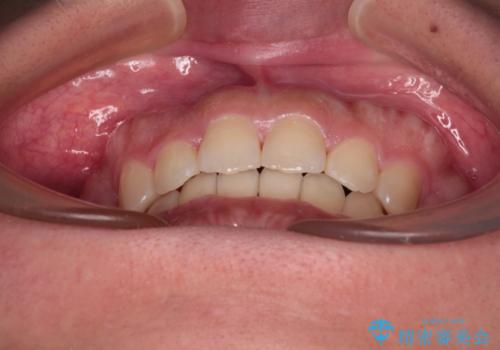

急速拡大とワイヤー抜歯矯正で唇を閉じやすく

- 口元の突出感を気にして来院された患者様です。

デコボコと口元の突出感が認められたため、上下左右の第1小臼歯4本を抜歯してのワイヤー矯正を行うこととしました。

上顎歯列の横幅が狭く、下顎大臼歯の歯軸が舌側に倒れていたため、急速拡大装置により上顎骨を側方に拡大し、咬み合わせを改善することとしました。

上顎歯列幅を拡大したことで、デコボコを容易に解消することができるようになったため、抜歯により得られたスペースを口元の突出感改善に利用することができました。